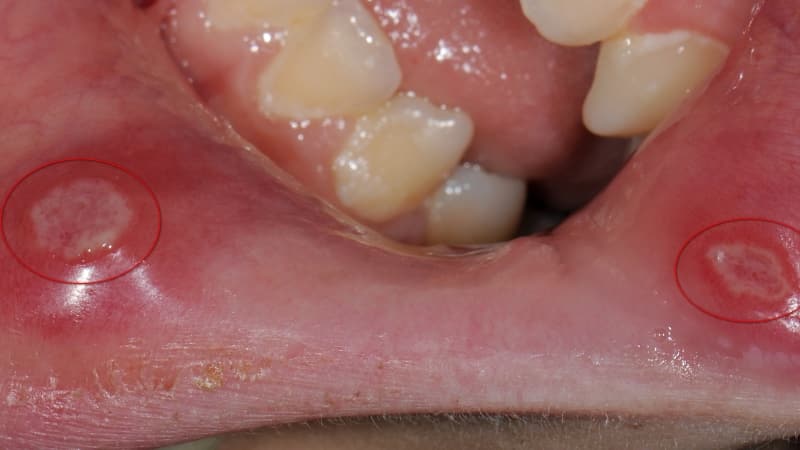

Поражения в ротовой полости могут проявляться в различных участках, таких как десны, щеки, небо и язык. Их формирование может занимать от семи дней до нескольких месяцев, в результате чего возникают новообразования с быстрым делением клеток. Причины такого явления могут быть разнообразными, и в медицине это состояние называется лейкоплакия. Одной из основных причин появления белых поражений является неправильный выбор зубной пасты или ополаскивателя для рта.

Одним из ключевых факторов, способствующих образованию белесых участков, является воспалительный процесс в ротовой полости, известный как стоматит. Существует несколько типов этой патологии: